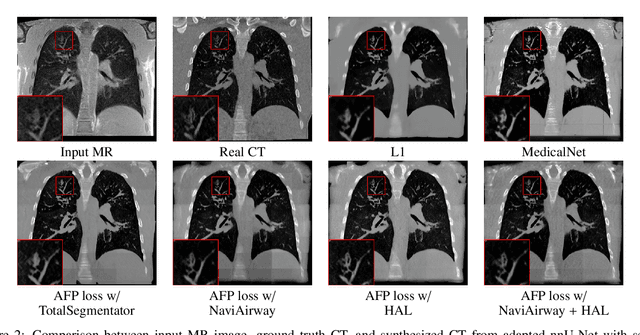

Abstract:In medical image synthesis, the precision of localized structural details is crucial, particularly when addressing specific clinical requirements such as the identification and measurement of fine structures. Traditional methods for image translation and synthesis are generally optimized for global image reconstruction but often fall short in providing the finesse required for detailed local analysis. This study represents a step toward addressing this challenge by introducing a novel anatomical feature-prioritized (AFP) loss function into the synthesis process. This method enhances reconstruction by focusing on clinically significant structures, utilizing features from a pre-trained model designed for a specific downstream task, such as the segmentation of particular anatomical regions. The AFP loss function can replace or complement global reconstruction methods, ensuring a balanced emphasis on both global image fidelity and local structural details. Various implementations of this loss function are explored, including its integration into different synthesis networks such as GAN-based and CNN-based models. Our approach is applied and evaluated in two contexts: lung MR to CT translation, focusing on high-quality reconstruction of bronchial structures, using a private dataset; and pelvis MR to CT synthesis, targeting the accurate representation of organs and muscles, utilizing a public dataset from the Synthrad2023 challenge. We leverage embeddings from pre-trained segmentation models specific to these anatomical regions to demonstrate the capability of the AFP loss to prioritize and accurately reconstruct essential features. This tailored approach shows promising potential for enhancing the specificity and practicality of medical image synthesis in clinical applications.